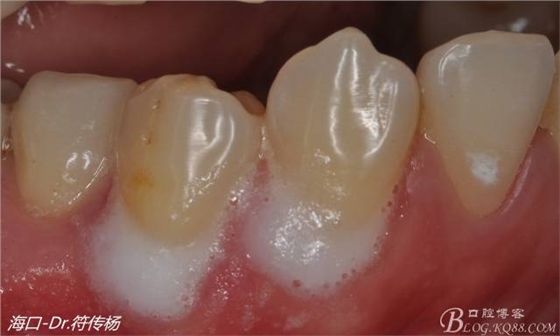

然后使用EDTA處理根面2min利于牙周附著(有爭(zhēng)議)

關(guān)于根面涂釉基質(zhì)蛋白可增加附著質(zhì)量爭(zhēng)議較少 但不幸的是國(guó)內(nèi)暫無(wú)此類產(chǎn)品出售